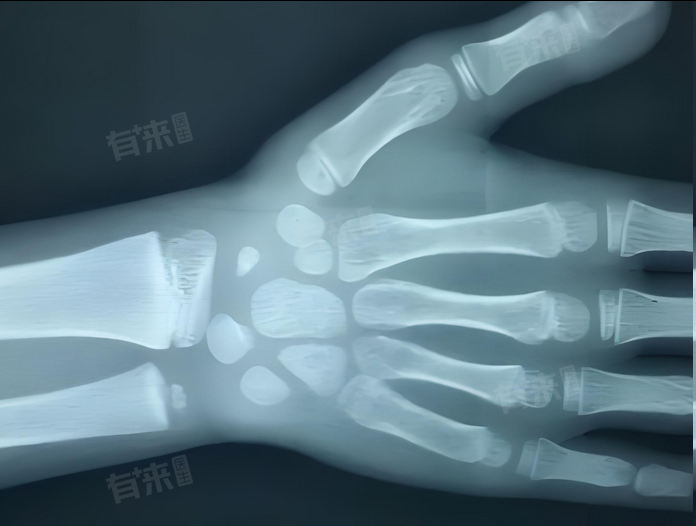

骨化中心数量可辅助判断骨龄,通常情况下,骨化中心7枚大致对应7-8岁骨龄,但并不绝对,会因个体差异及评估方法不同而有波动。

1、通用标准参考:在常见的骨龄评估体系中,如Greulich-Pyle图谱法,儿童在成长过程中,骨化中心按一定顺序和时间出现。一般到7-8岁时,手腕部等部位的骨化中心数量接近7枚,以此作为初步判断依据。

- 在儿童生长过程中,骨骼最初以软骨形式存在,随着时间推移,特定部位的软骨开始骨化,形成骨化中心,并且按一定顺序在不同年龄段出现。

- 骨化中心数量随年龄增长而增加,通过统计骨化中心数量,可初步估算骨龄。例如,新生儿通常只有1-2个骨化中心,到10岁左右,手腕部骨化中心可达10个左右,以此对应相应骨龄阶段。

- 不仅骨化中心数量重要,发育程度也与骨龄相关,骨化中心从出现到完全骨化,经历不同阶段,如早期为点状,逐渐增大、融合。医生通过观察骨化中心的形态、大小、密度等发育程度,更精确判断骨龄。